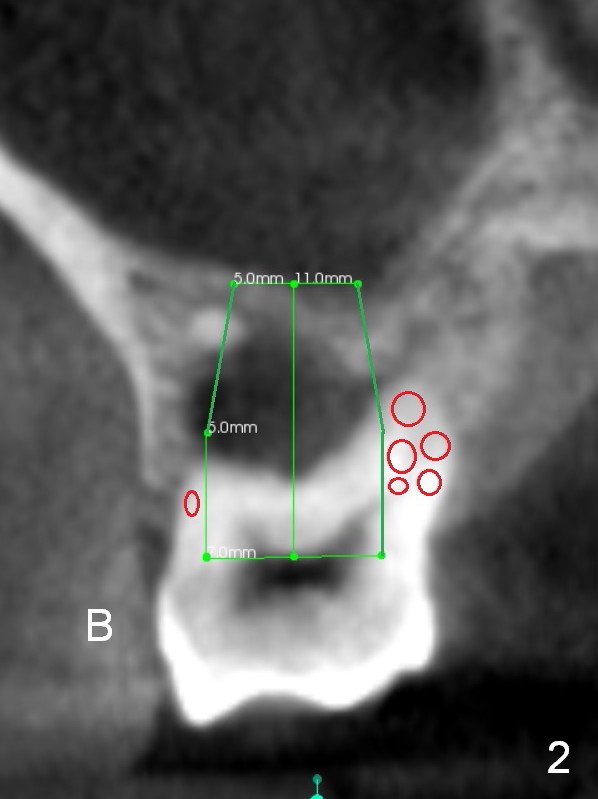

A 52-year-old lady (ZJ) has severe bone loss at #3 (Fig.1 (CT sagittal section)). After extraction, the socket will be treated with Metronidazole. A small amount of apical bone is available for primary stability; the bone density is also low (300-500 Hounsfield Units, Fig.3 (axial section)). Use RT2,3 for creating osteotomy and bone condensation, followed by 4.5-7x14 mm taps (11 mm deep; gingival margin). Prior to bone grafting (Fig.1,2 (coronal section) red circles), apply Endogain against the root surface of the neighboring teeth.